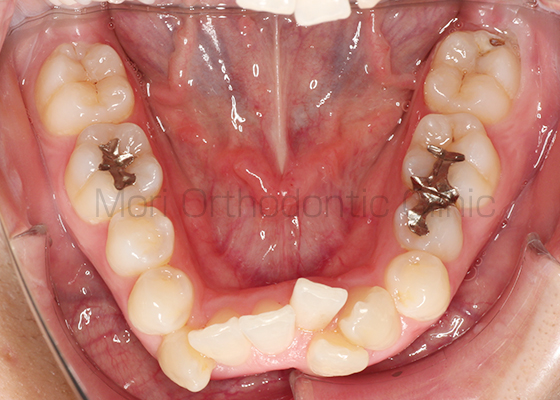

術前

術後

| 主訴 | 出っ歯、歯並びが悪い |

|---|---|

| 診断名 | AngleⅠ級叢生 |

| 年齢 | 21歳11か月 |

| 治療装置 | Multi-Bracket(フルリンガル) |

| 抜歯部位 | 14,24,34,44 |

| 治療期間 | 2年7か月 |

| 治療費 | 1,180,200円(税込) |

| リスク・副作用 | 矯正治療による歯の移動に伴う痛み、歯根吸収、歯肉退縮、虫歯 |